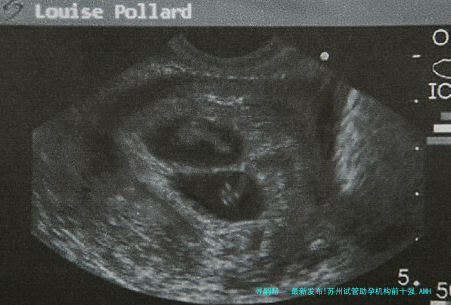

当清早的缕太阳光穿透薄雾,洒在姑苏古城白墙黛瓦的院落里,一张写着“AMH值0.3”的诊断单却让窗边的影子微微发抖——这是许许多多渴望生育的家庭一起面对的无声战斗。抗缪勒管激素(AMH)的断崖式着落,曾被看作生育期望的终结,但2025年姑苏辅助生殖技术的创新正在编写结局:微刺激方案、人工智能胚胎筛查、线粒体体激活等前端技术,让卵巢储存枯竭的女性仍有机缘迎来新生。科学的医院选择策略,恰是翻开这扇希望之门的重点钥匙。

> 当一颗AMH 0.2 ng/毫升下的4AA级囊胚成功着床时,那些曾被宣判的“不可能”,终将在技术翻新中重写为生命的新章。